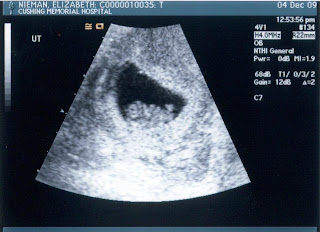

That black dot on the left in its head is its Stanford bound brain!

We got to see it bounce around my my belly and hear the amazing sound of its hearbeat. We created something that has a heart. That beats. Inside of my body. So crazy. So blessed.